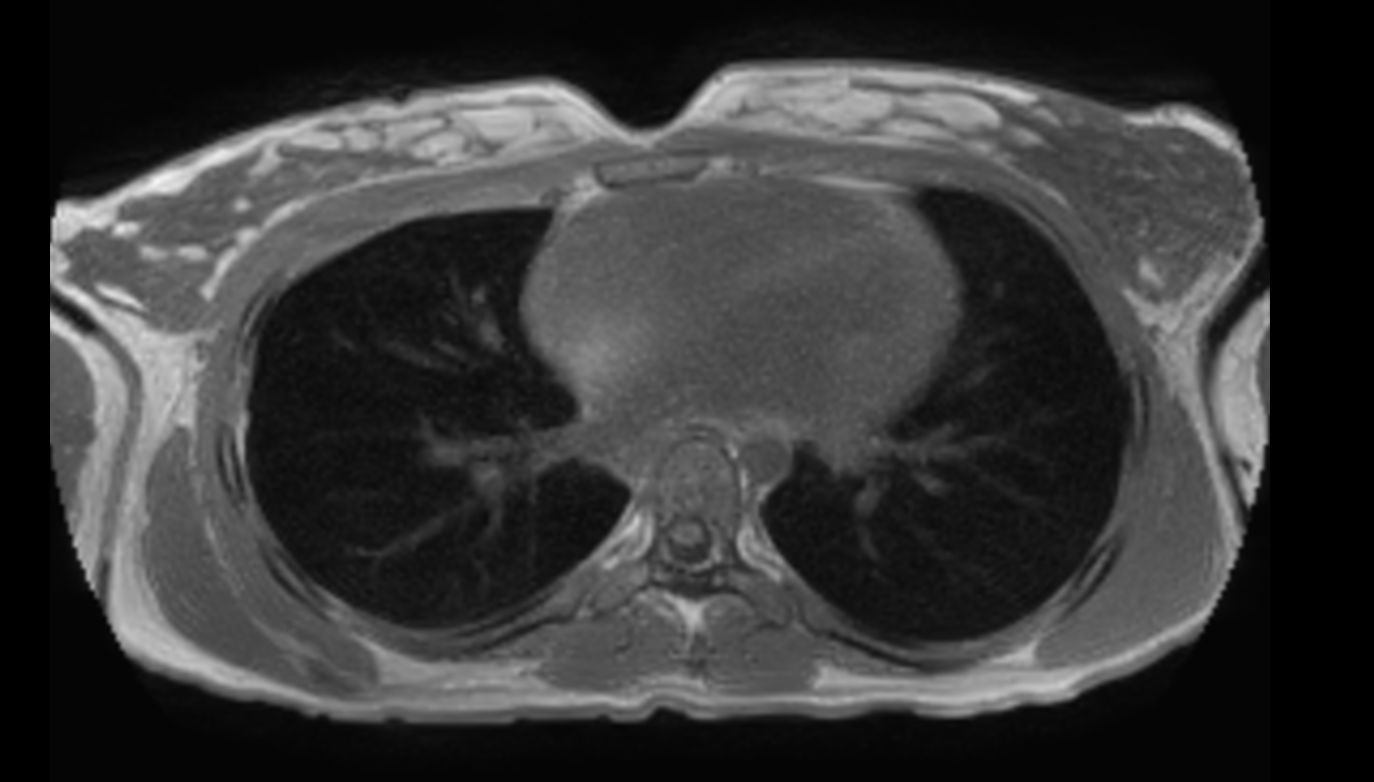

T2w SPIR - MultiVane XD